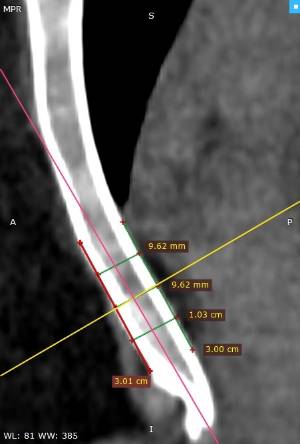

Les dades mèdiques del pacient, més l'exploració clínica realitzada per l'equip de cirurgia, juntament amb una anàlisi detallada de les imatges del TAC i les reconstruccions digitals en 3D de cada tòrax realitzades conjuntament amb l'equip d'enginyers de Ventura Medical Technologies, són la base per determinar si la tècnica Pectus Up està indicada i com cal procedir en cadascun dels pacients.

Amb aquestes dades se selecciona l'implant que millor s'ajusta a l'anatomia de cada tòrax, la ubicació exacta del sistema d'elevació i, alhora, proporciona a l'equip quirúrgic un detall dels passos que cal tenir en compte per fer-ne una correcta implantació.

Pectus Excavatum Pectus Excavatum Asimétrico Índice de Asimetría 0.6 (+R/-L)(|AI|> 0.05 Asimétrico) Índice de Haller 4.5 (HI >3.5) Índice de Corrección 49.13% Rotación esternal 18.1 ° (a la derecha)

Informe d'avaluació del TAC d'un pacient enviada al cirurgià